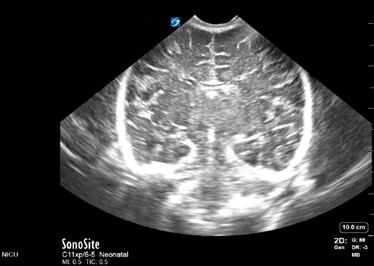

Neonatology Normal Anatomy Gain Too High Image